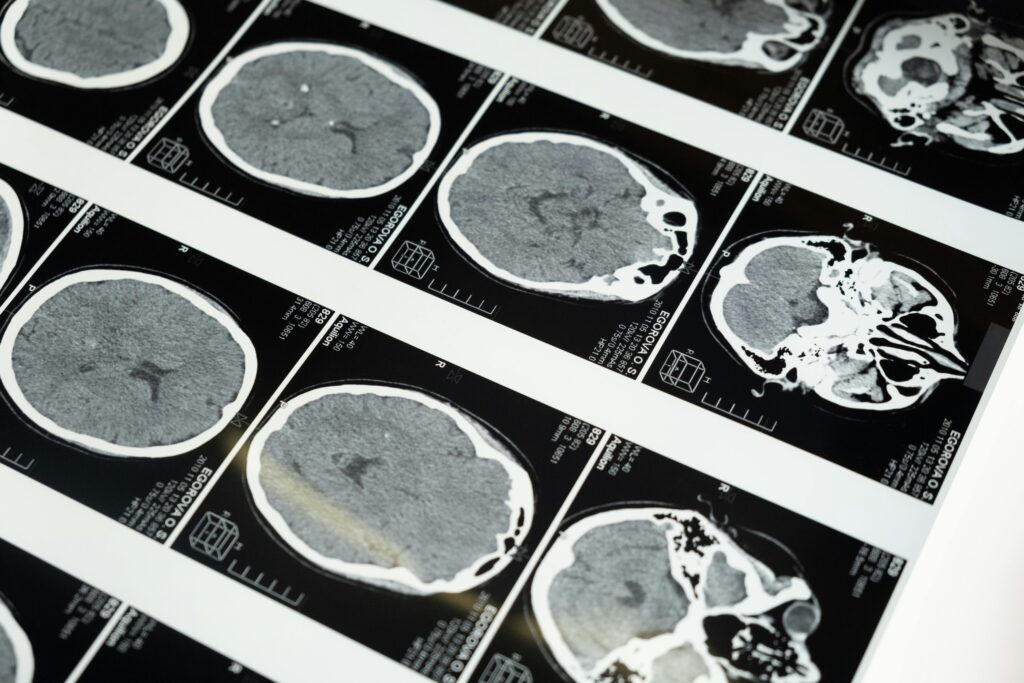

كيف يدرس علم النفس العصبي الدماغ؟

يعتمد هذا العلم على مجموعة أدوات تشخيصية وبحثية متقدمة، أهمها:

- الإصابات الدماغية